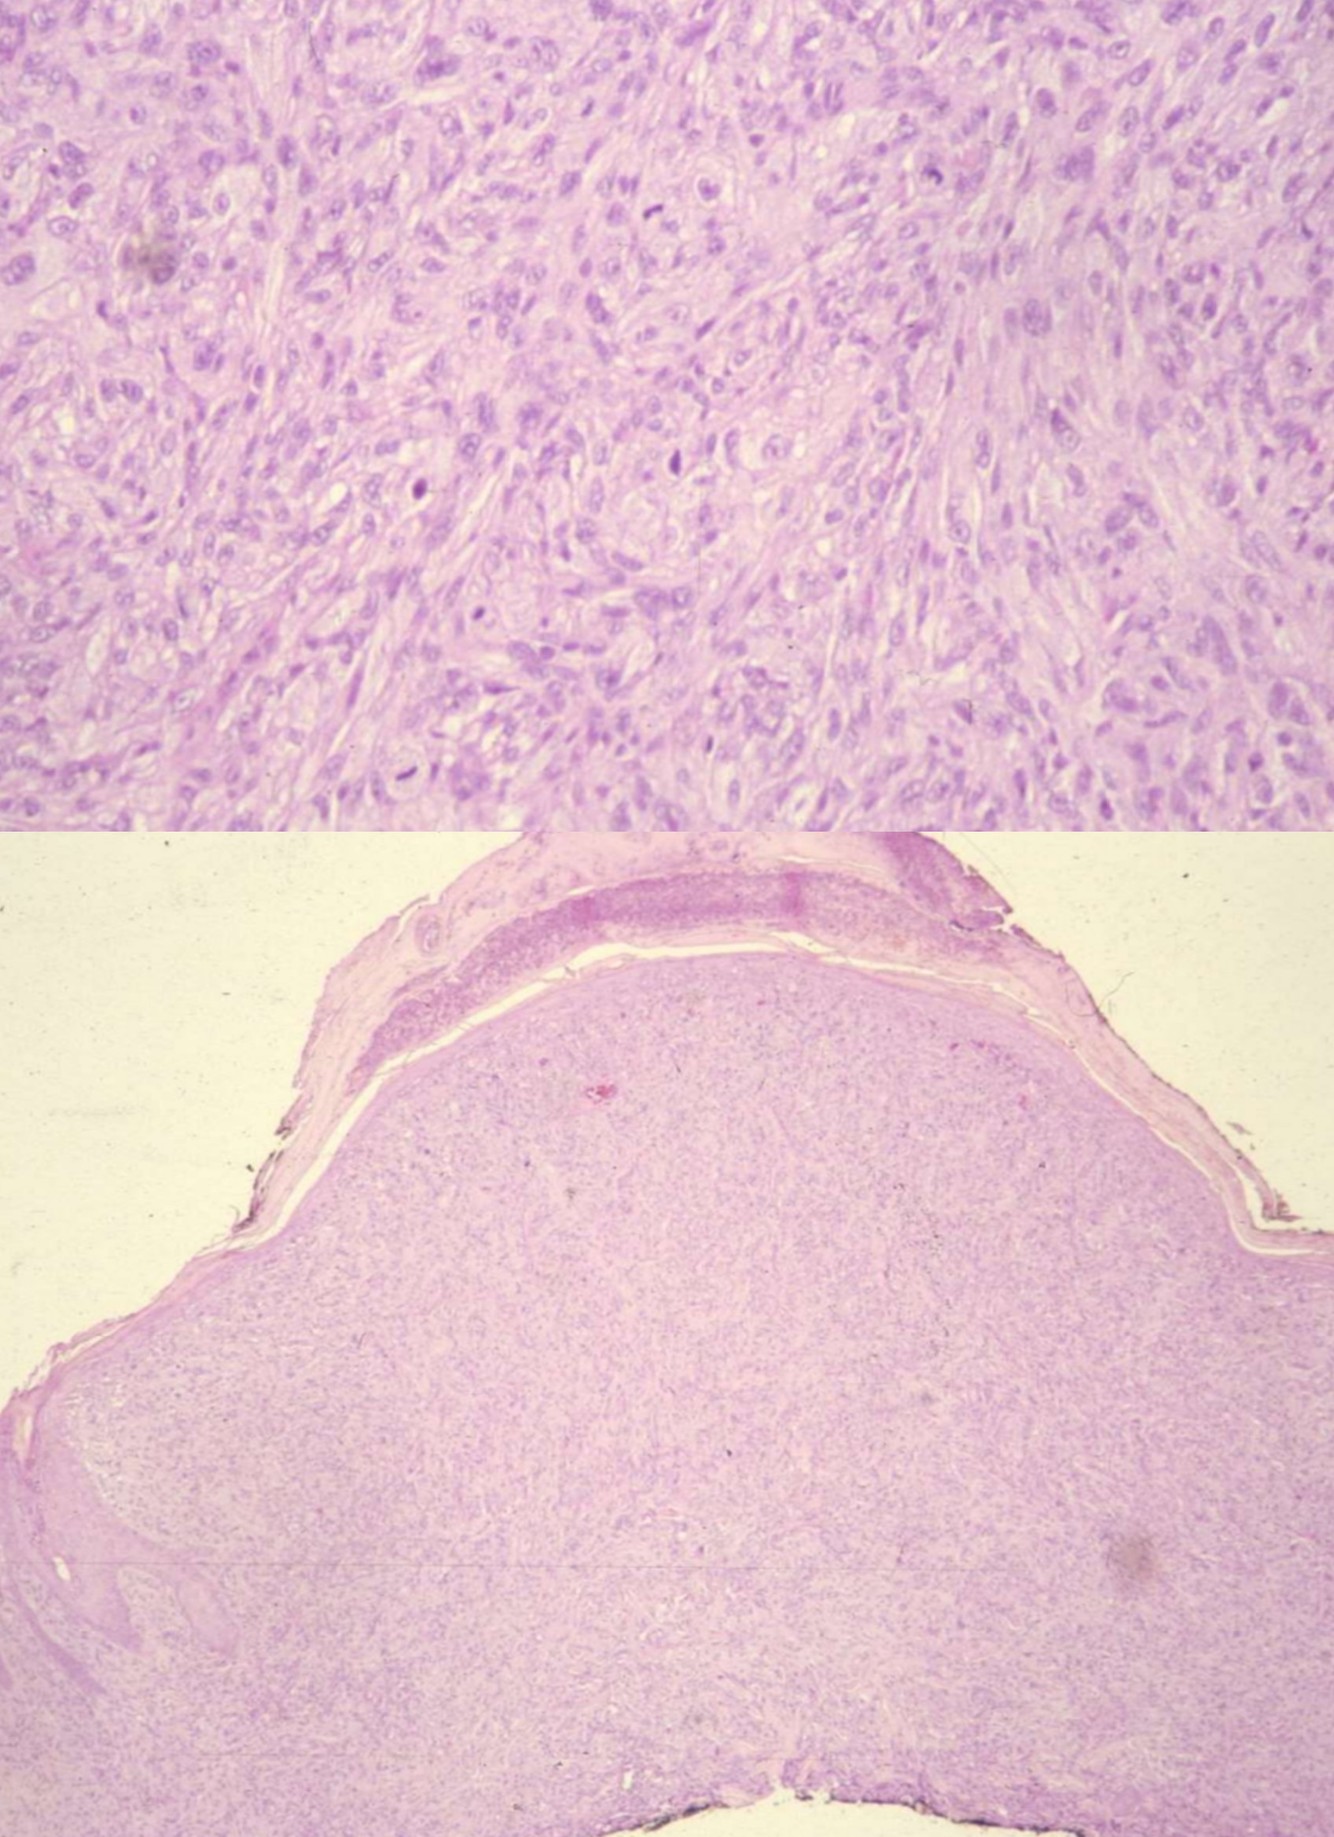

ATYPICAL FIBROXANTHOMA

• Seen primarily in the elderly population

• Predilection for sun-exposed skin, especially scalp and ear

• MFH-like tumor of the dermis

• Histology

• Well circumscribed, appears symmetric at scanning magnification

• Bizarre multinucleated tumor cells in hypercellular, spindly stroma with frequent mitotic figures, many atypical

• Also smaller fibroblastic, myofibroblastic and histiocyte-like cells with pleomorphism and angulated nuclei

• Histologically identical to MFH-pleomorphic but centered in dermis

• Background stroma appears inflammatory or reactive

• Pushes aside pilosebaceous units and eccrine glands

• Typically does not involve epidermis or subcutaneous tissue

• Lacks classic features of fibrous histiocytoma (entrapped hyalinized collagen bundles and epidermal hyperplasia)

• No grenz zone, no necrosis, no vascular invasion, no infiltrative margins

• Stains

• Positive: Vimentin, and p53

• Negative: Cytokeratin, S-100, Desmin or smooth muscle actin, LN-2 antibody (CD74)

• Diagnosis of exclusion – need to exclude the diagnosis of melanoma

• Excellent prognosis